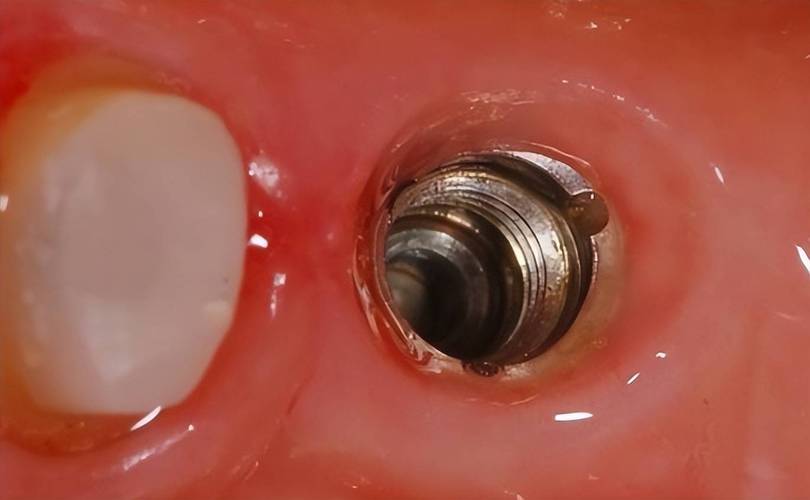

植入种植体:

- 当窝洞预备完成后,医生将纯钛或钛合金制成的种植体(通常带有螺纹)旋入或敲入预备好的窝洞中。

- 关键要求:

- 初期稳定性: 种植体植入后必须获得良好的初期稳定性,这是骨结合成功的基础,医生会通过手感、敲击声音或扭矩扳手确认稳定性。

- 深度: 种植体植入的深度需达到预设的生物学宽度要求,并确保植入位置正确(通常平台位于牙槽嵴顶或略低于骨面)。

- 方向: 与备洞方向一致,符合最终修复设计。